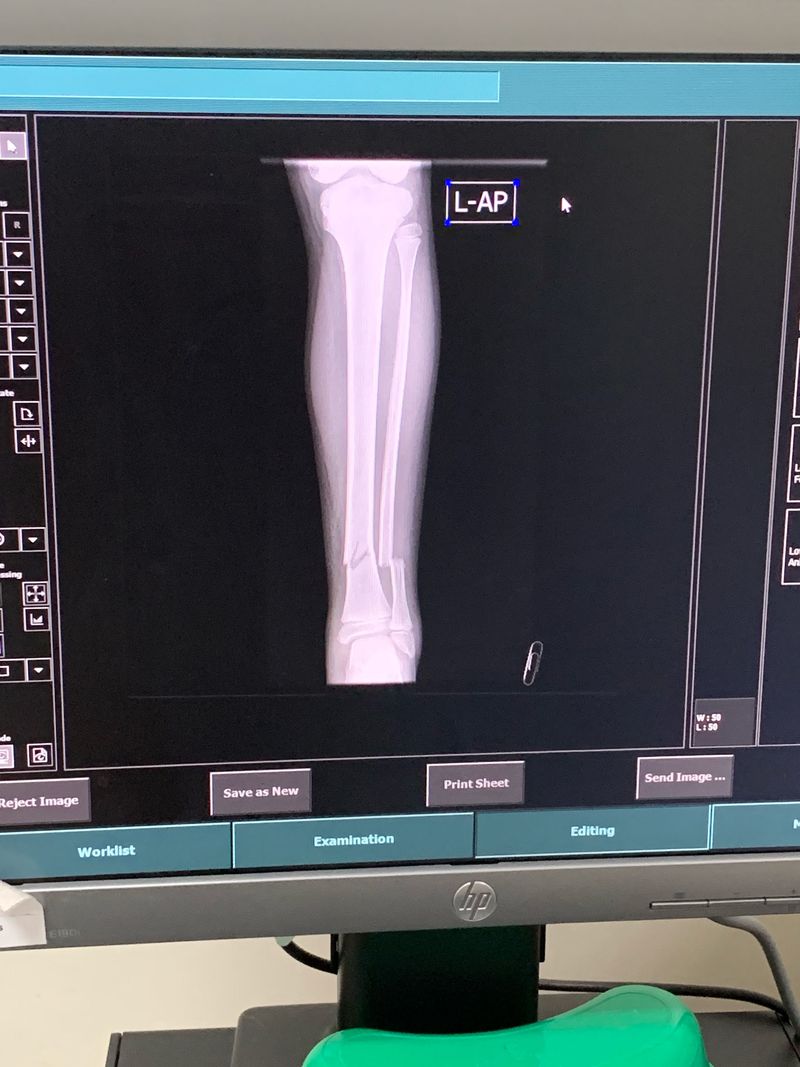

Update: he was advised for closed fixation and fiber glass cast from the left ankle to the half of the thigh. Doctor said if the patient is 12 years old above he is candidate for operation. He is advied also for bed rest up to 5 weeks. And for xray once on follow up. Thanks